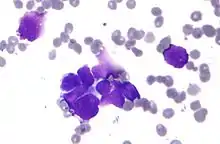

- Malignant melanoma